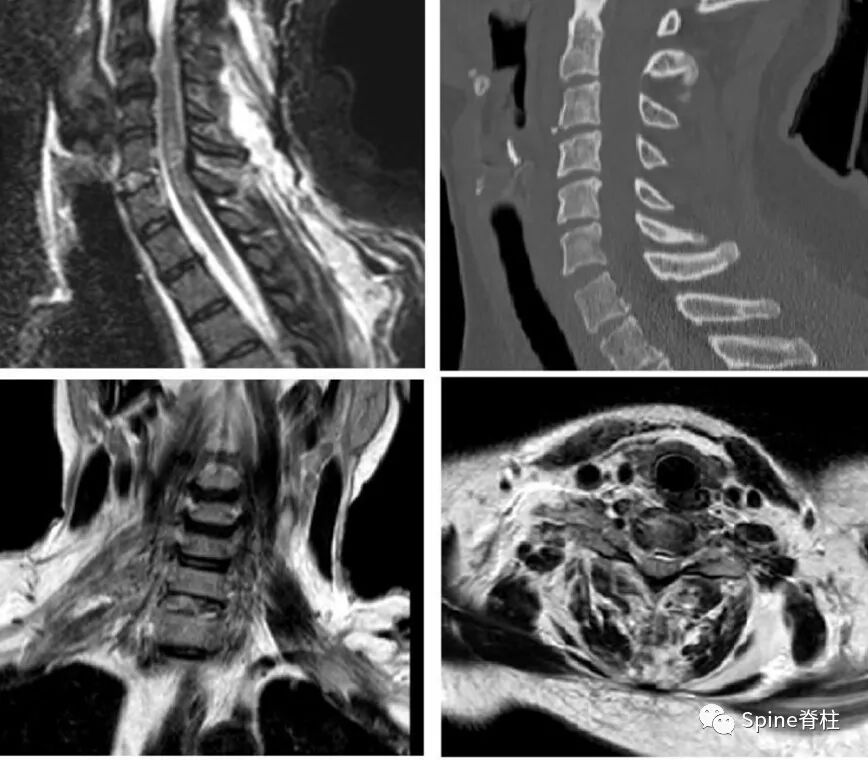

患者31岁,男性,车祸后导致C4-5脱位伴脊髓损伤,行自体髂骨移植融合加钢板内固定术。术后7年出现渐进性吞咽闲难,2个月后出现干咳及发热。颈椎X线片示咽后间隙积气,钡餐检查示巨大袋状食管憩室(图1a),CT显示食管后壁和椎前间隙相通(图1b)。消化道内镜检查发现钢板和螺钉突入食管内。手术取出前路钢板及螺钉,清创后切除憩室,胸骨舌骨肌及肩胛舌骨肌肌瓣修补食管(图1c)。术后留置鼻胃管进行肠内营养10 d后拔除鼻胃管,常规抗生素使用7 d,抑酸。患者于术后2周出院,术后佩戴颈托4周,恢复良好。

图示:颈椎外伤后C6-7脱位,前纵韧带断裂